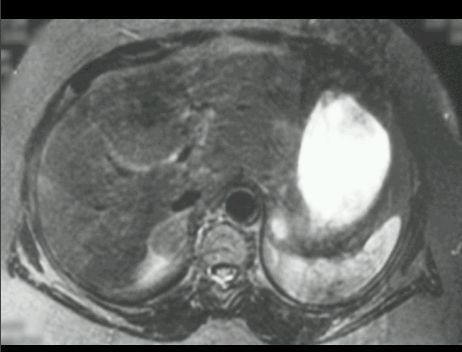

GRUCZOLAK NADNERCZA

MR